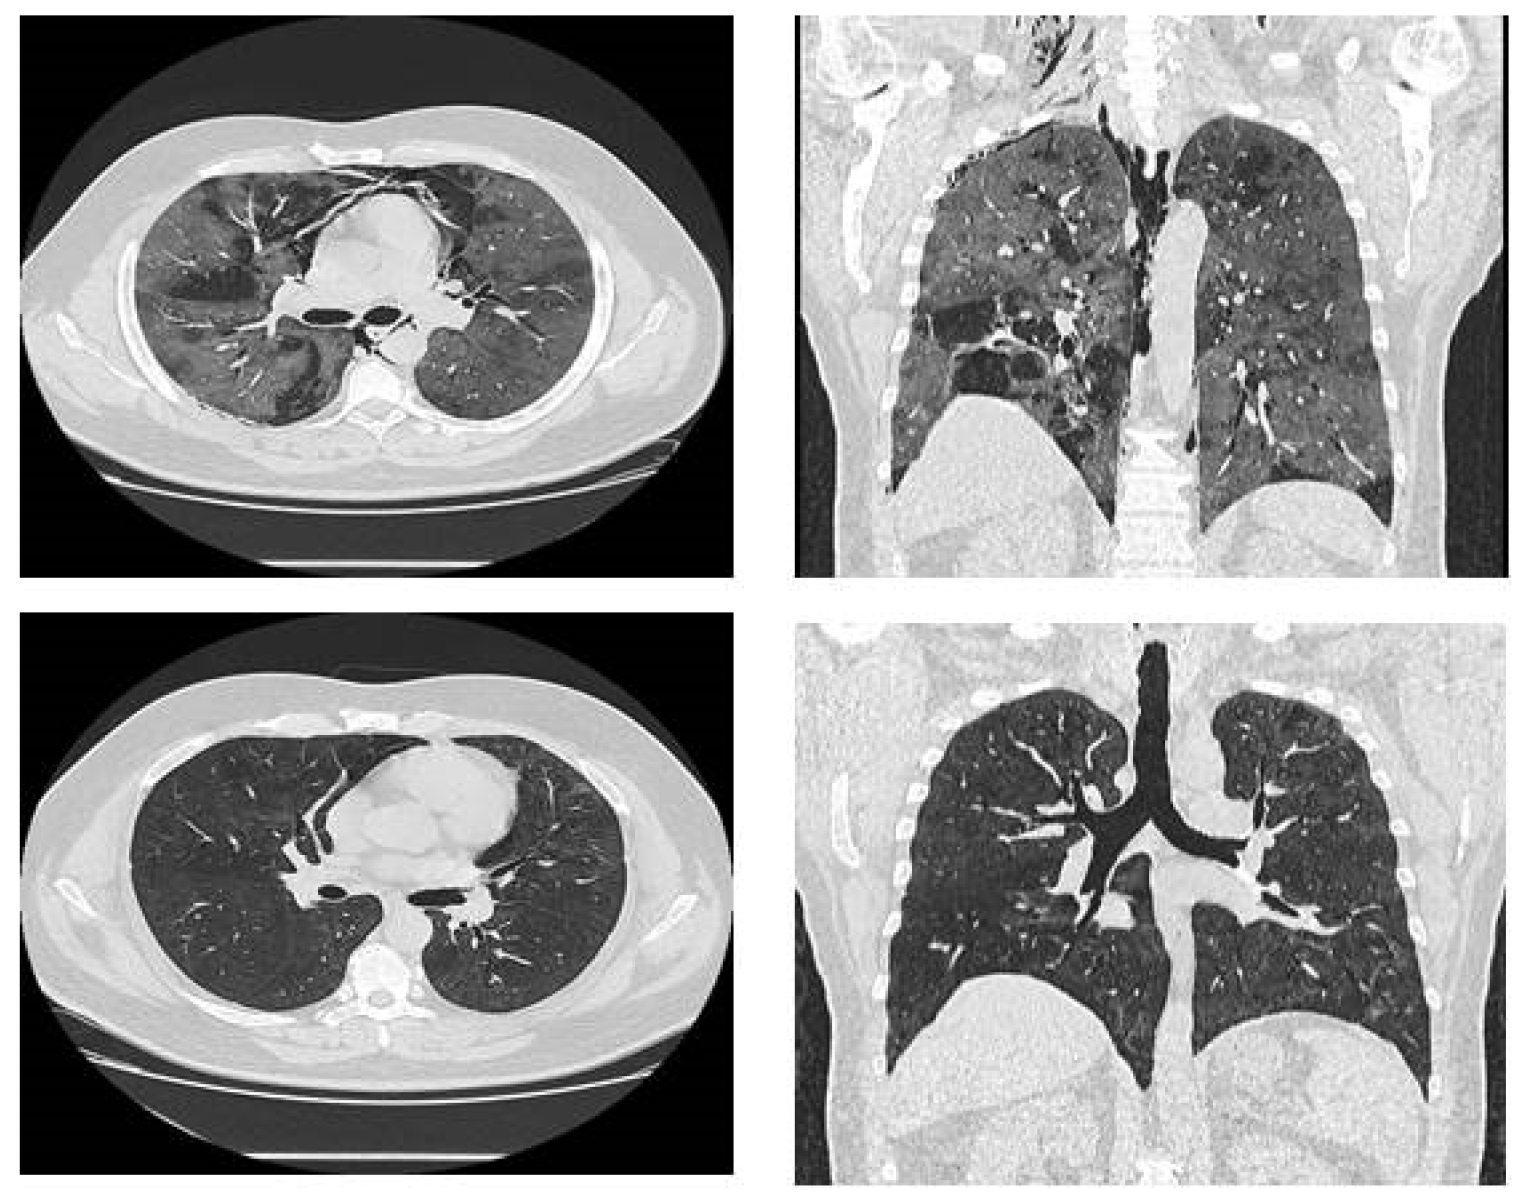

Massive Spontaneous Pneumomediastinum—A Form of Presentation for Severe COVID-19 Pneumonia

Case Presentation